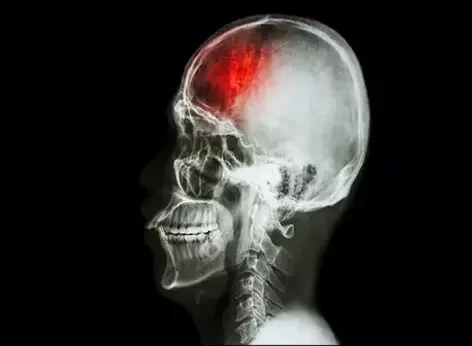

Winters are on the edge and the problems of stroke are increasing gradually. Protecting yourself in winter is wisely said as people are more prone to diseases. Every year more than 800,000 people suffer a stroke, especially in winter.

Studies have found that cold weather increases the risk of stroke. As a result of cold weather, blood vessels constrict and blood pressure rises, which is a major risk factor for stroke.

Even in winter blood tends to get thickened and stickier which makes it easier to clot. Many stroke cases are due to blood clotting that blocks a blood vessel to the brain. With more studies, researchers have discovered a pattern of stroke rates that is higher in winter months, and lower in summer with a temporary spike in July month.

According to studies that have been done on countries with diverse seasons such as Finland, Australia, the United States, Germany, Taiwan, China, and Iran. It was reported that strokes happen more often in colder seasons than in warmer months. This risk of stroke occurs because thickened blood causes blood clots that stop the flow of blood in a particular area of the brain.

The accumulation of blood clots in a particular area of the brain will gradually decrease the oxygen supply to the brain. It forces the heart to increase the blood flow to maintain the oxygen level for the entire body. However, a massive clot will result in a stroke. If you experience any of the following causes of strokes in winter, consult a neurologist in Udaipur.